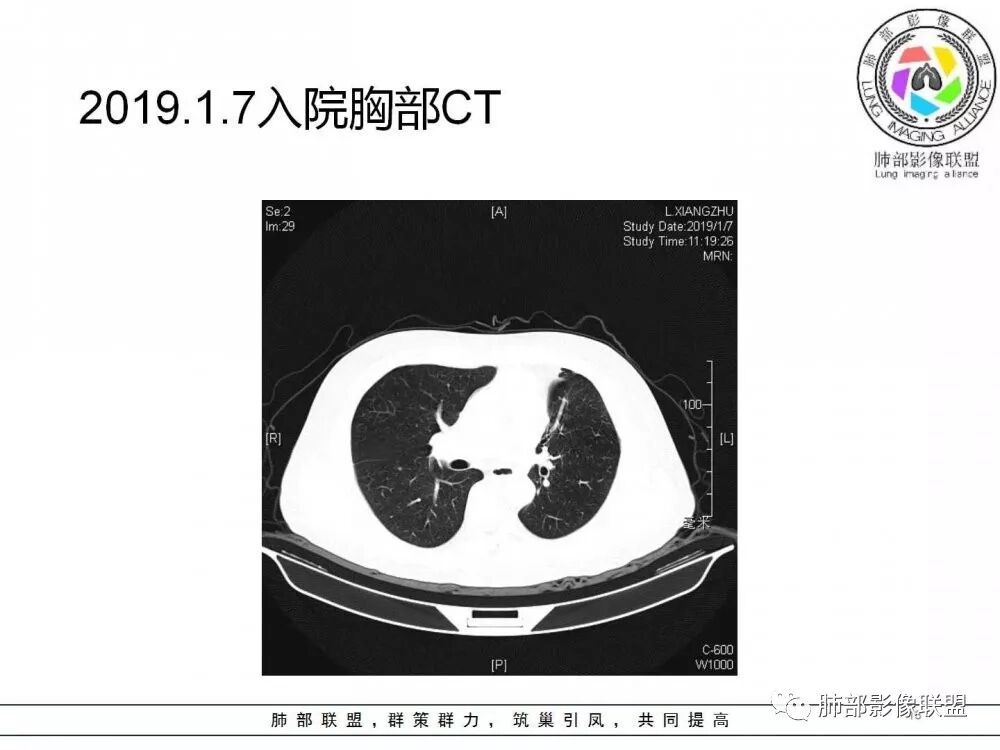

病灶从2月份就开始有,应该最早说是1月7号就有了,到3月13号稍微增大一点,到后面几乎没变化,到5月份好像稍微大一些,炎性应该是炎性,犹豫的是这个炎性到底什么病变呢?其实本没变化,它特点一个是在叶裂上,跟血管关系密切,但是病灶边缘稍收缩,病灶没有太大变化。